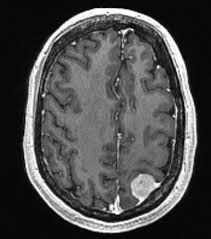

1. При показании к радиохирургии, специалист-радиохирург проводит предварительную оценку, рассматривает снимки КТ или МРТ, осмотр пациента, изучение медицинской истории, с учетом всех методов лечения в прошлом, особенности питания пациента и его лекарственной чувствительности, а также сопутствующих заболеваний.

Пациент должен проходить регулярную томографию (МРТ), обычно один раз в год, таким образом наши специалисты контролируют изменения в опухоли.